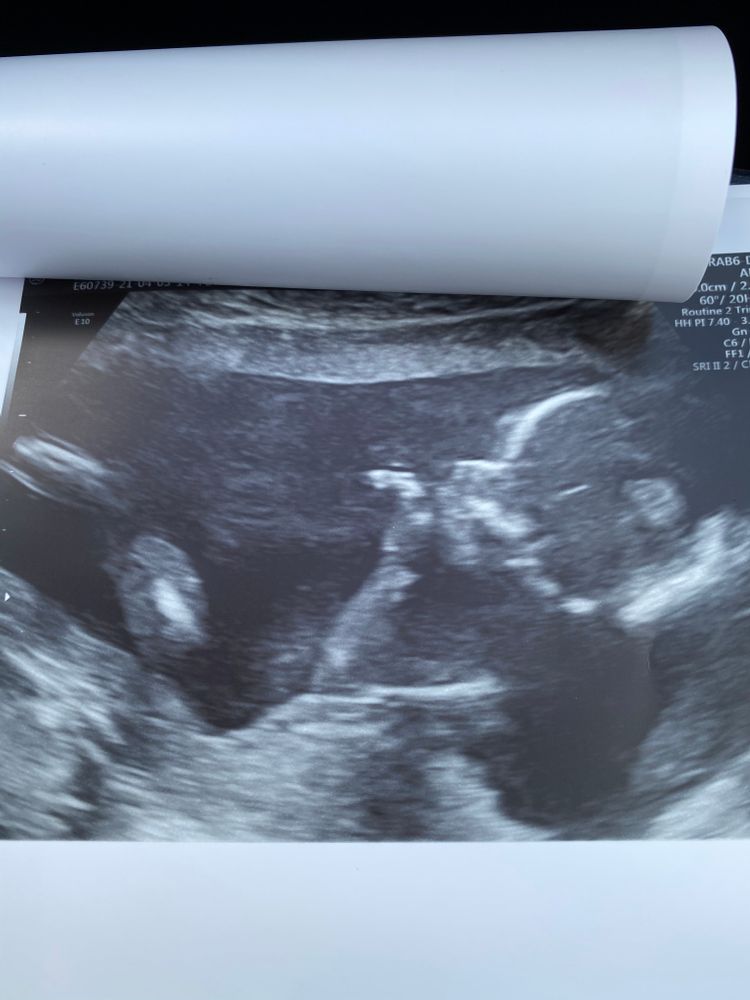

Экспертное узи 16+3💙

УЗИ, КТГ, доплерВчера были на экспертном узи, все показатели отличные и соответствуют срокам, твп в норме и носик тоже, врач успокоила. Наш малыш первым делом сразу всем сообщил, что он гражданин, а не гражданка 😃 помахал ручкой, растрогал папку (тёр глаза, но теперь отрицает 🙈)